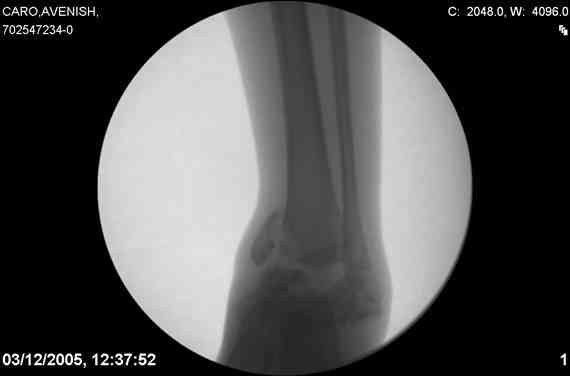

ya by popytalsya sobrat talus anatomichno,seichas pozdno operirovat iz za oteka,po etomy distrakziya apparatom budet optmalna.Posyalu vam podobyai moi sluchai.

14 years old girl

Fall from height ( 3rd floor)

Compressed fractures of L1-L2

Fx of orbital bone

Mark, судя по снимкам в день поступления произведен А.В.Ф., а остеосинтез ч-з какое время произведен?, остеосинтез произвели открытым способом?( на снимке п/о рубцы).

aparat postavlen v den postupleniya,rastaynuli, vpravili zakryto naskolko vozmoghno, a kogda otek spal sdelali otkrytoe vpravlenie.Teryat tut nechego, moghno tolko uluchshit.